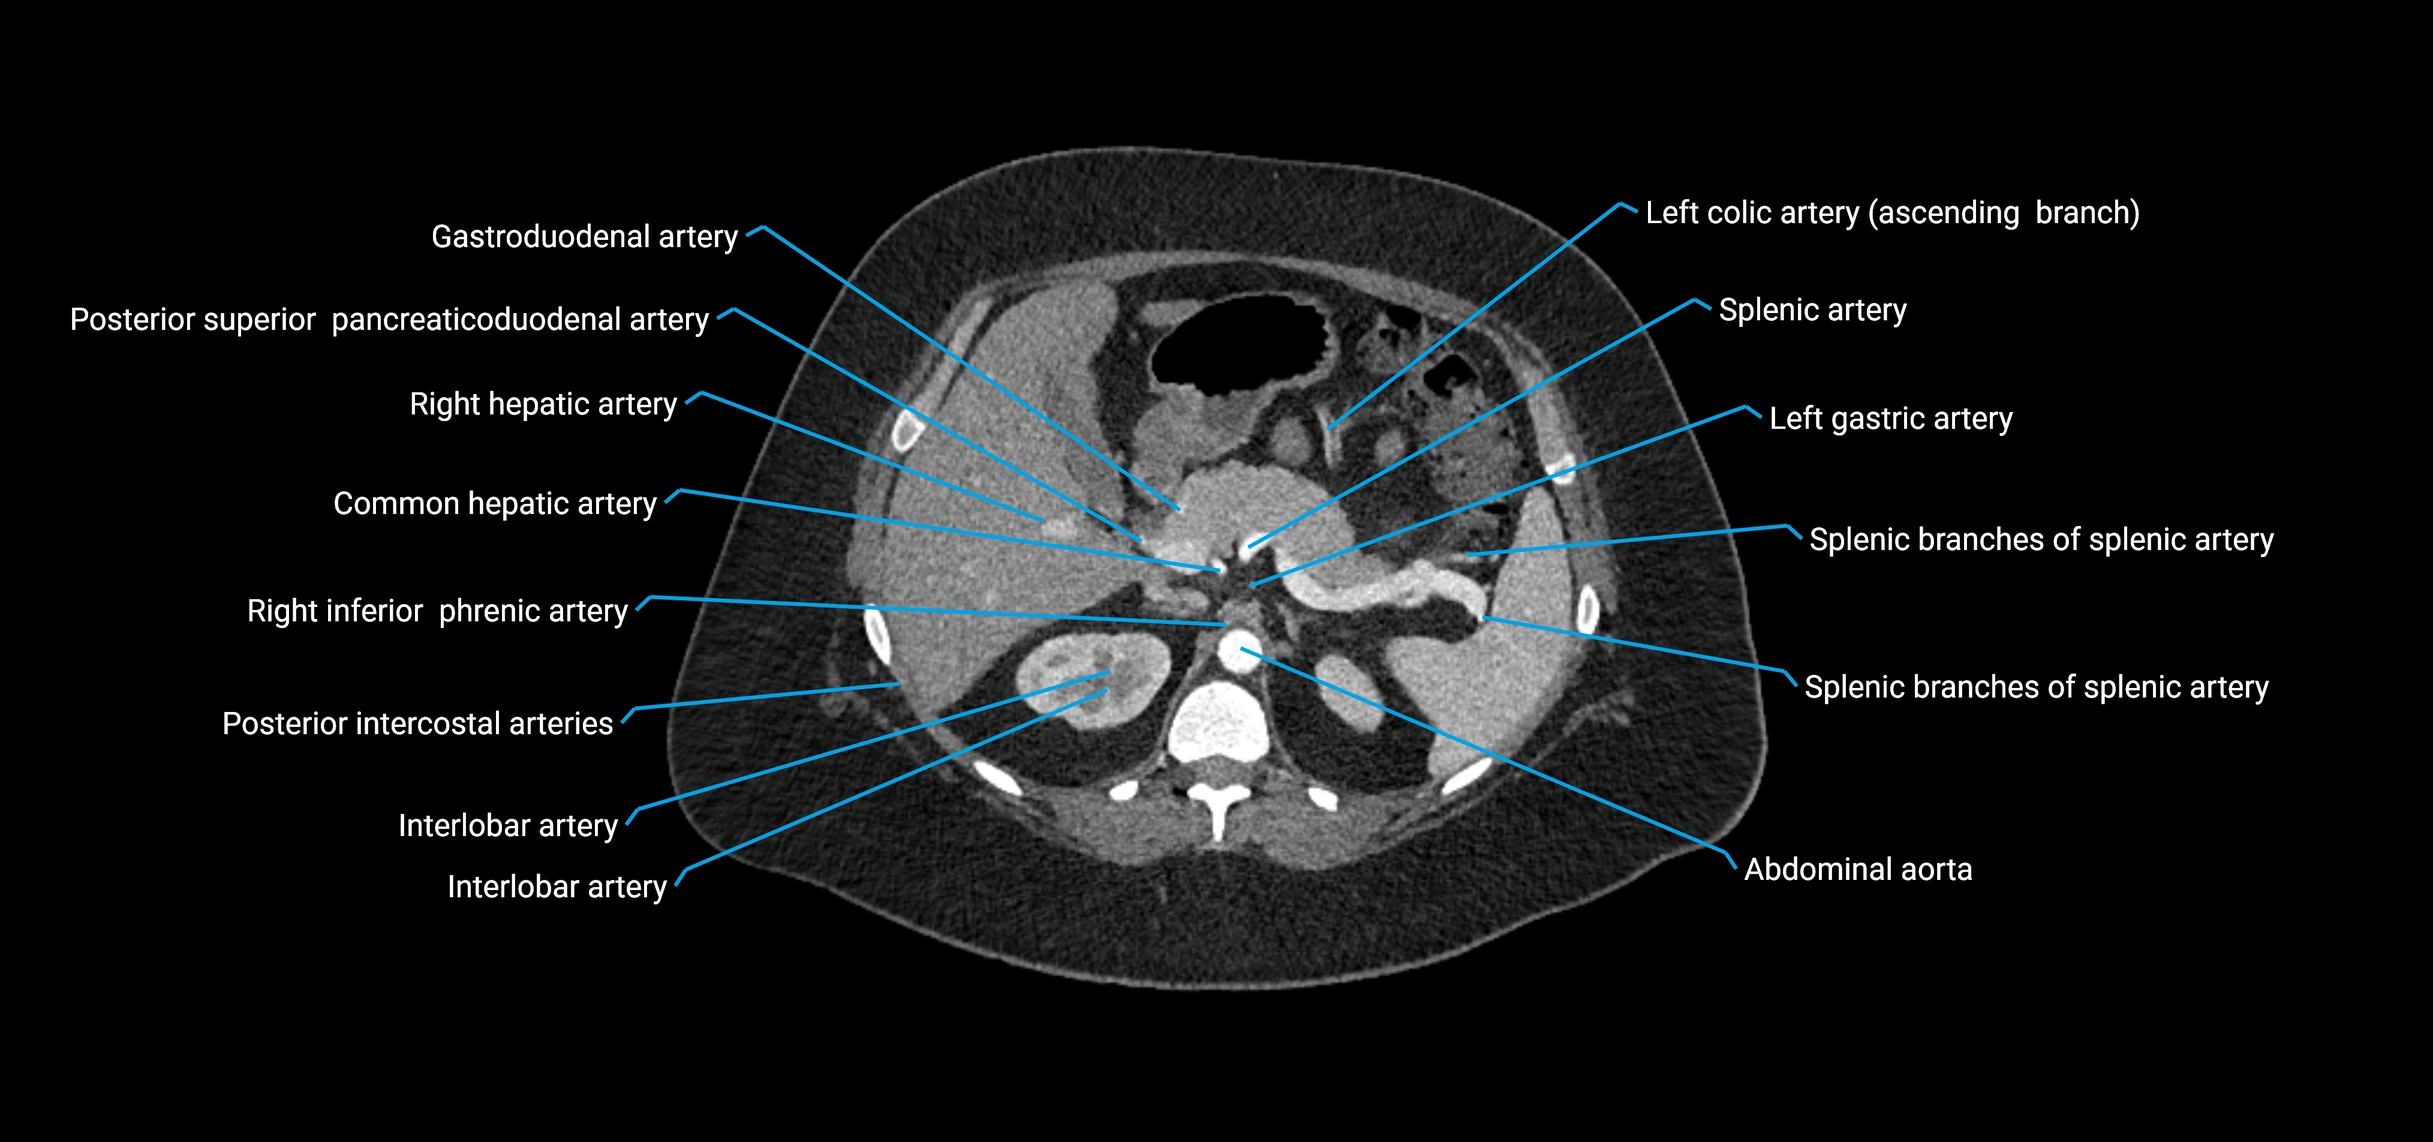

CT images

image

Contrast-enhanced CT (CTA):

• Gold standard for abdominal aortic imaging

• Provides excellent detail of lumen, wall, aneurysm, thrombus, and branch vessels

• Multiplanar and 3D reconstructions help in aneurysm measurement, stent graft planning, and dissection evaluation